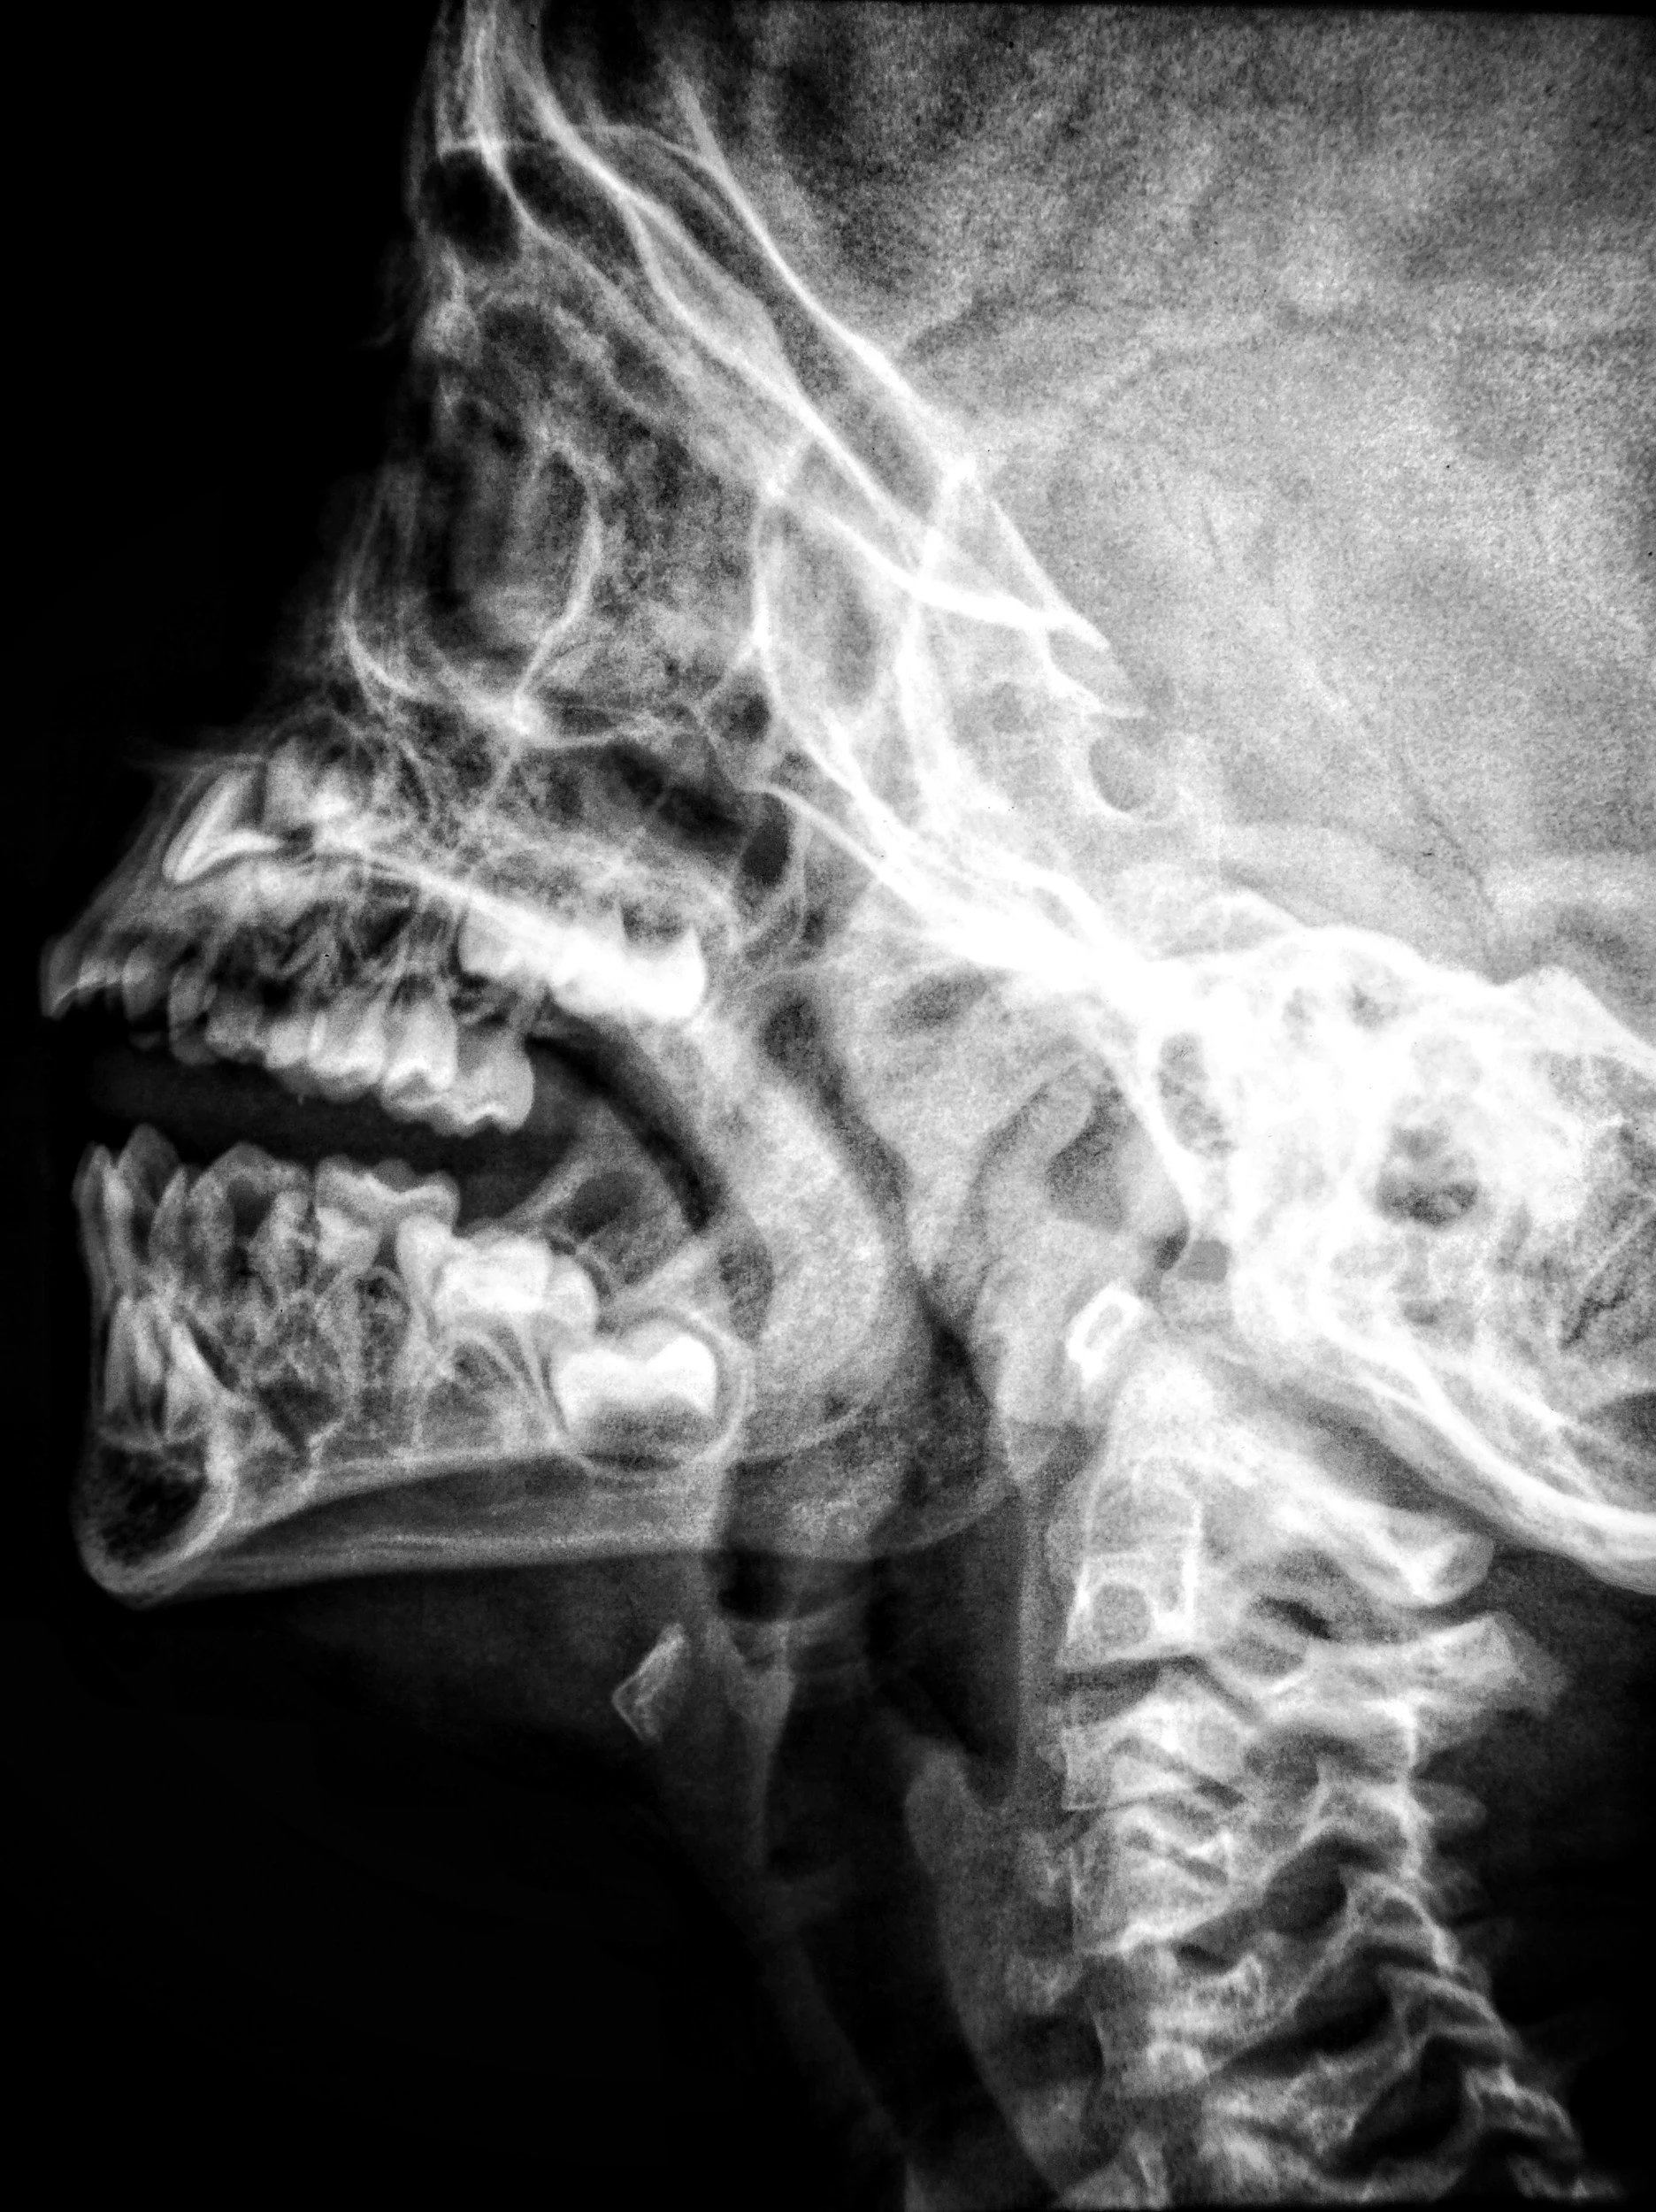

What Is TMJ Dysfunction?

TMJ (temporomandibular joint) dysfunction refers to issues affecting the jaw joint and surrounding muscles. This joint connects your jaw to your skull and plays a key role in speaking, chewing, and breathing.

When the joint or muscles are not functioning properly, it can lead to pain, tension, and restricted movement.